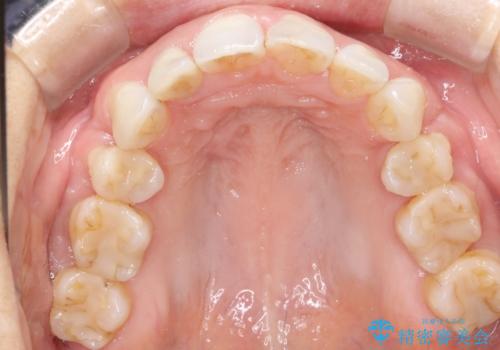

- 上下の歯のがたつきを主訴に来院されました。

上下の前歯の叢生とかみ合わせが深い過蓋咬合という状態でした。

上下左右の歯を1本ずつ抜歯して、ワイヤーにて矯正を行いました。